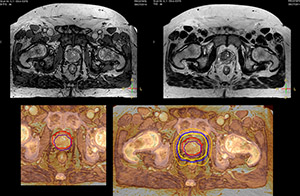

“The biggest problem for CT-based planning, especially in prostate, is you can’t see the cancer very well,” says Dr. Stevens. “On CT it can be quite challenging to see the edge of the prostate especially at the apex. When the edge of the prostate can’t be delineated well on CT, radiation oncologists will increase their margins a little bit so they don’t miss it, but that can also increase toxicity.” “Using MR, the prostate is well delineated. We quickly see the edges of cancerous tumors like in prostate cancer, and as normal structures can be defined, we can optimize the treatment plan to protect these organs and their normal function. This can potentially improve the outcome. And it improves workflow as well. We can contour more quickly, confident that the tumor is going to be in the field.” “The Ingenia 3.0T MR scanner provides high resolution allowing us to make scans fast for the patients. It also gives the potential to include methods like MR spectroscopy and diffusion weighted Imaging, which we’re in the process of doing right now,” Dr. Stevens adds.

“When a patient registers, first CT simulation and MR simulation are done, followed by CT-MR registration on Pinnacle3. Then the target and normal organ delineation is performed on MR images. Meanwhile we create a reference CT image for online treatment and localization correction. During the treatment phase we can perform additional MRI scans to visualize the anatomy changes and create an adaptive plan. This plan basically adapts the treatment plan to the changes.” “Along with its great benefits, MR has introduced some new challenges,” Dr. Stevens says. “Radiation therapy teams generally have no experience with MR. The Philips training helped us to implement fully the things we can do with the Ingenia MR-RT system. So the training, as well as having a good MR physicist, is critical.”